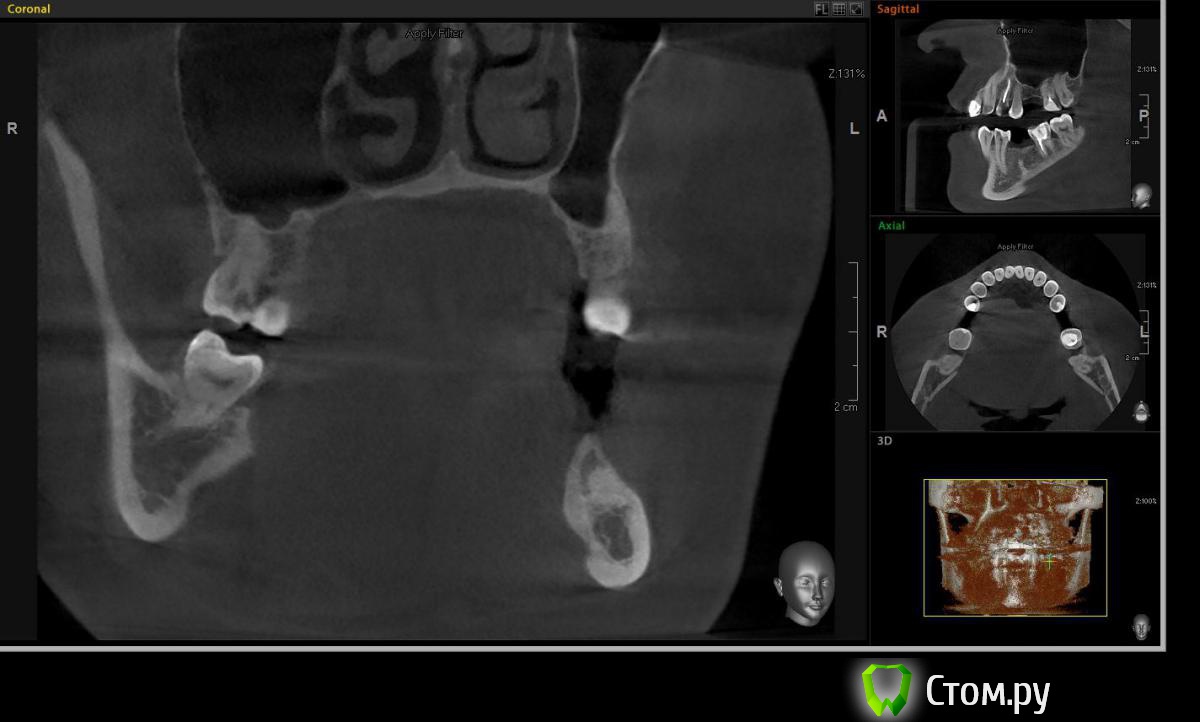

Евгений Ходыкин Опубликовано 19 октября, 2014 Поделиться Опубликовано 19 октября, 2014 Всем привет. Кто сталкивался подскажите плиз что за образование и как отразится на постановке имплантата. Вроде подобное что-то обсуждалось, но перестрахуюсь Ссылка на комментарий

Чертков Александр Опубликовано 20 октября, 2014 Поделиться Опубликовано 20 октября, 2014 Остеома или конденсирующий остит. На имплантацию никак не повлияет. Повлияет вестибулярный дефект гребня 2 Ссылка на комментарий

Михаил Демурчян Опубликовано 24 октября, 2014 Поделиться Опубликовано 24 октября, 2014 (изменено) Похоже на гиперцементоз. Возможно также, имеется осколок корня удаленного 3.6. Изменено 24 октября, 2014 пользователем Михаил Демурчян Ссылка на комментарий